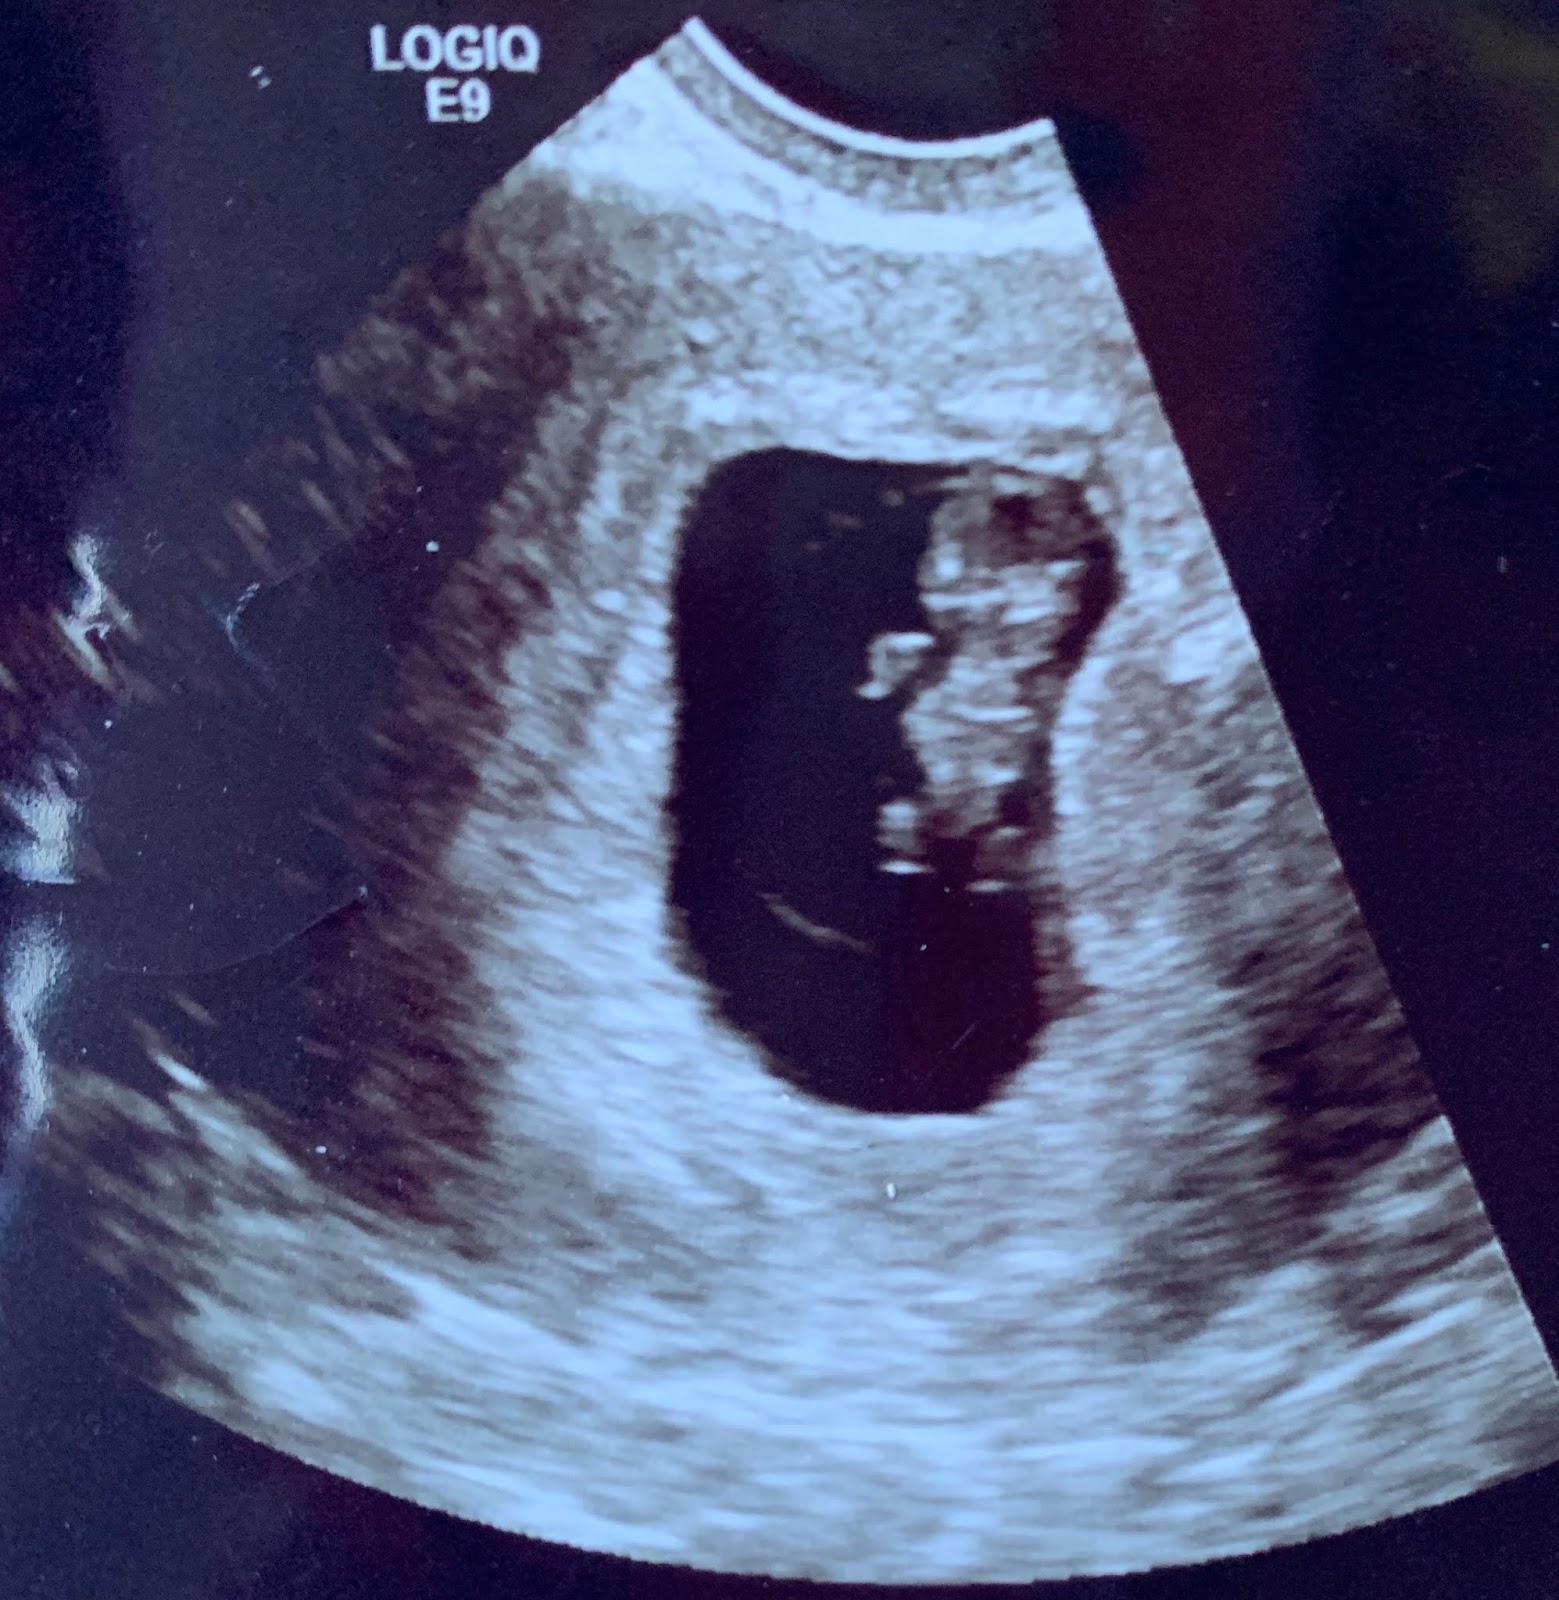

Baby Chris is Seven Weeks Old

Seven weeks after fertilization, Baby Chris has brainwaves! In fact, brainwaves have been detected by EEG as early as six weeks and two days.

Baby Chris’s heart, which has been beating since 18 days after conception, now has a more matured four-chamber structure. It now beats between 167 and 175 times per minute; it will decline to about 140 beats per minute at birth.

Fingers and toes are starting to separate but are still somewhat webbed. Until now, Baby Chris’s skeletal system has consisted solely of cartilage and membranes, but that is beginning to change as bones ossify in the collar bone and jaw. Also appearing by seven weeks: taste buds, elbows, and hiccups!